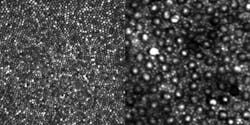

Rods are much more numerous than cones and are vastly more sensitive to light. With the optical design method successfully demonstrated by Dubra's team, even the smallest cone cells at the center of the retina, known as the foveal center, can be seen very clearly. Rods can be seen clearly in a less central retinal location (see figure).

Though earlier AO systems could effectively image cones and have become a mainstay of high-resolution retinal imaging research, the smaller rods, which outnumber cones 20 to 1 in the retina, have eluded clear and contiguous observation in the living eye.

The breakthrough in the design of the AO instrument that led to clearly visualizing rods was, according to Dubra, "embarrassingly simple, and relied on well-known equations and concepts." By simply folding the spherical mirrors that act as lenses in the instrument into a three-dimensional structure, the image quality of the retina was improved sufficiently to clearly resolve the contiguous rod mosaic, as well as the entire cone mosaic at the foveal center.